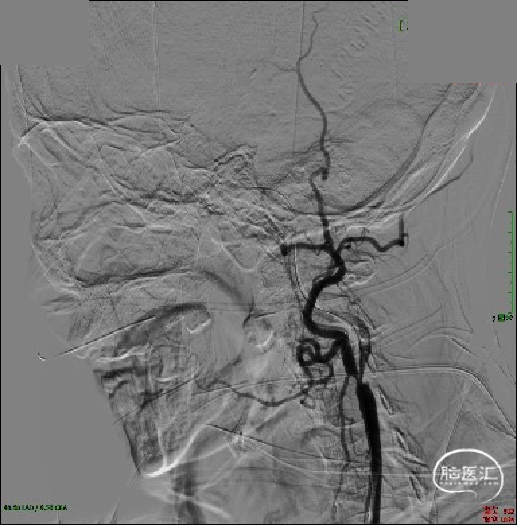

急诊DSA:主动脉弓造影提示LICA闭塞,RICA代偿差。

急诊DSA:LICA闭塞,LICA起始部次全闭塞。

急诊DSA:微导管于LICA-C2段造影见血栓近端所在,明确患者为LICA起始段次全闭塞合并远端栓塞的串联病变。